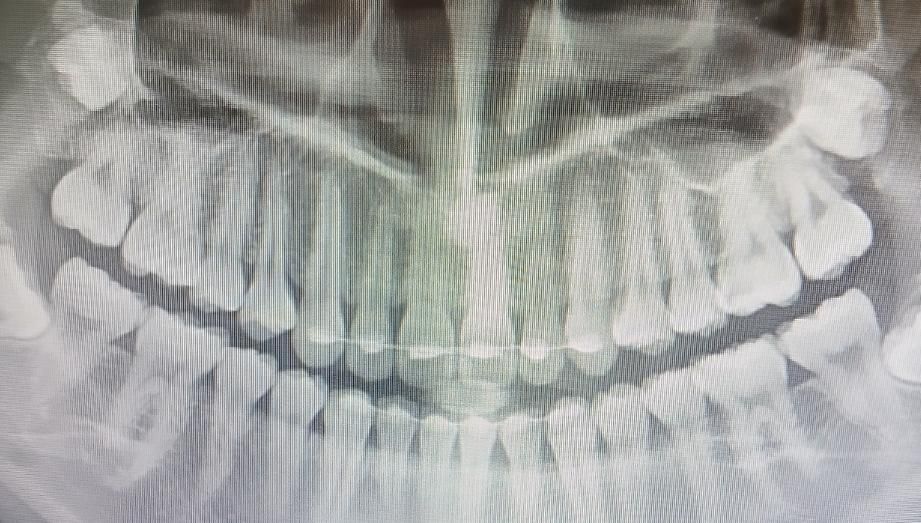

치아 엑스레이인데 충치 없다했는데 아파요ㅠ

한달전쯩 엑스레이인데 치과쌤이 충치 안보인다고 하셨거든요?? 근데 입 벌릴 때마다,그냥 있어도 왼쪽 어금니랑 잇몸사이가 아파요ㅠㅠ 엑스레이 상으로 충치 없는거 맞아요?

엑스레이 상으로 심각하거나 눈에 뛸만한 충치는 있어 보이진 않습니다. 잇몸이 안좋아서 그럴수 잇으니 잇몸치료를 받아보시는게 좋을것같습니다.

왼쪽 위 첫번째 큰 어금니가 약간 의심되긴 하나 그보다는 현재 맹출중인 사랑니가 통증을 유발하는 것일 수도 있을것 같습니다